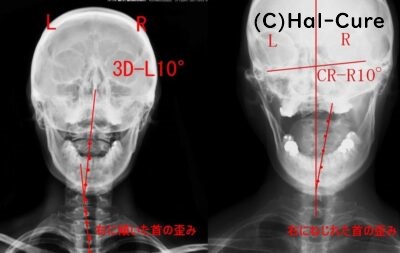

頸の歪みを戻すこと

首の傾きや捻じれを正常に戻す

歪み改善で関節への負担はかなり軽減できます

首の痛みがあった方は、矯正することで皆さん軽減しておられます

首の痛みで困っている方は、一度首の歪みを調べてみましょう